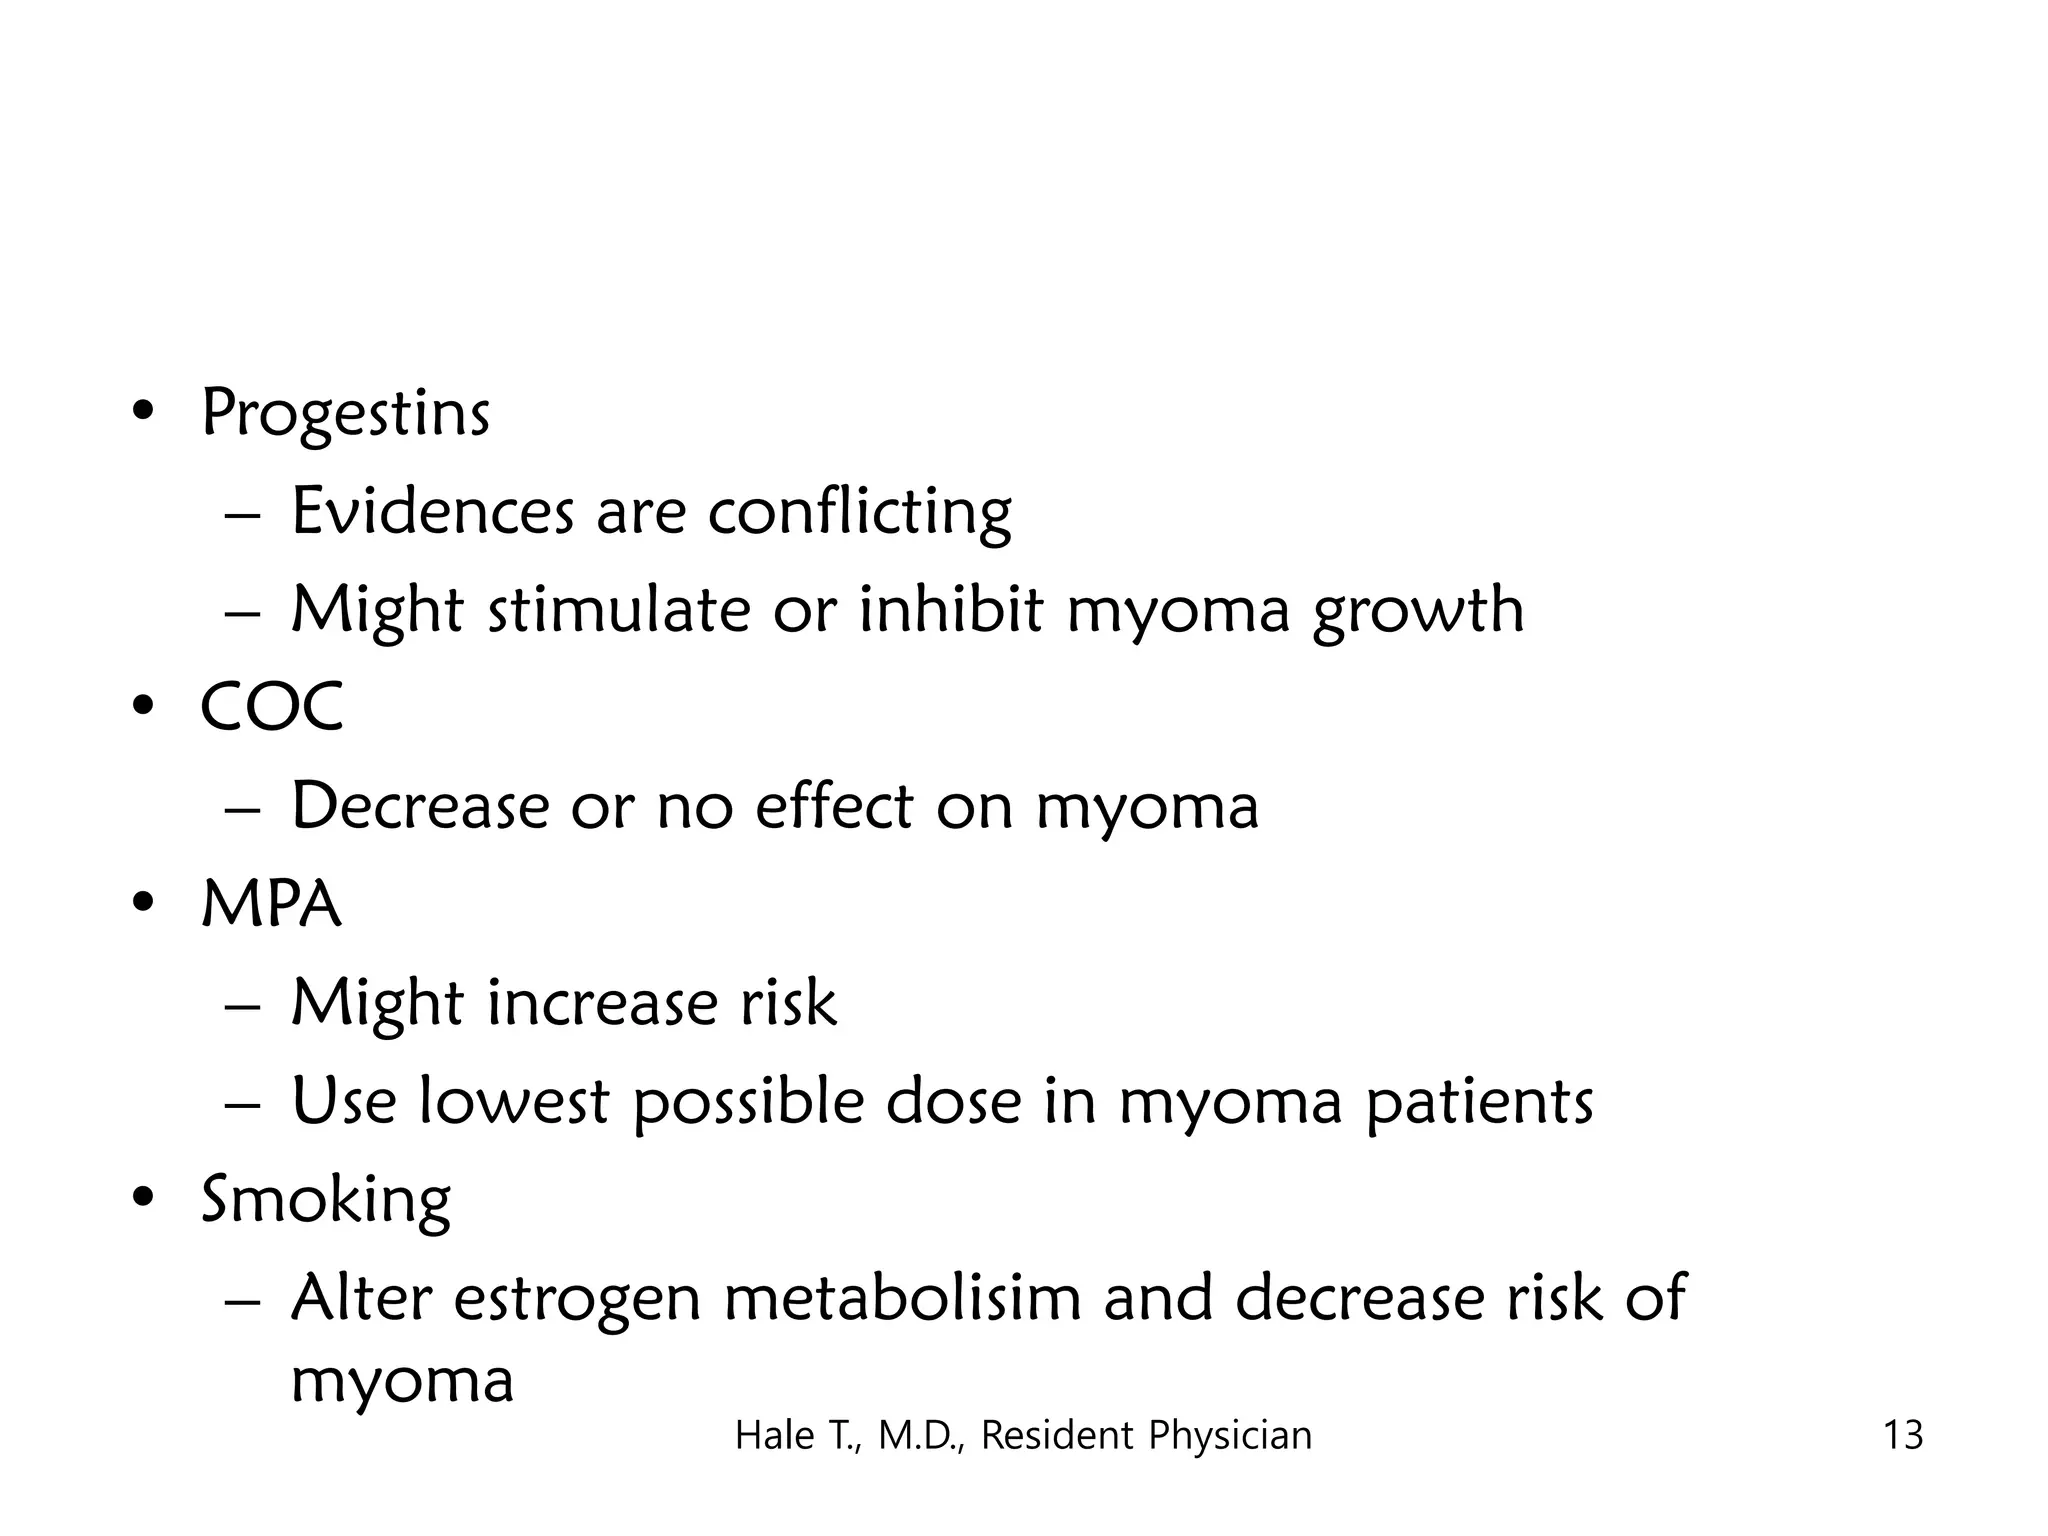

This document discusses myomas (uterine fibroids). It notes that myomas are benign smooth muscle tumors that originate in the uterus and are sensitive to estrogen and progesterone. Symptoms can include bleeding, pain, pressure, and infertility. Diagnosis is usually made through imaging like ultrasound or MRI. Treatment options include observation, drug therapy, uterine artery embolization, or surgical removal of the fibroids. The document also discusses complications that can arise if fibroids are present during pregnancy, such as pain, bleeding, preterm birth, and pregnancy loss.